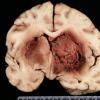

1B3 Artifact, frozen 3 half midbrain (L) into formalin without thawing vs fixed (R) (Case 2) H&E 5 whole mount 3